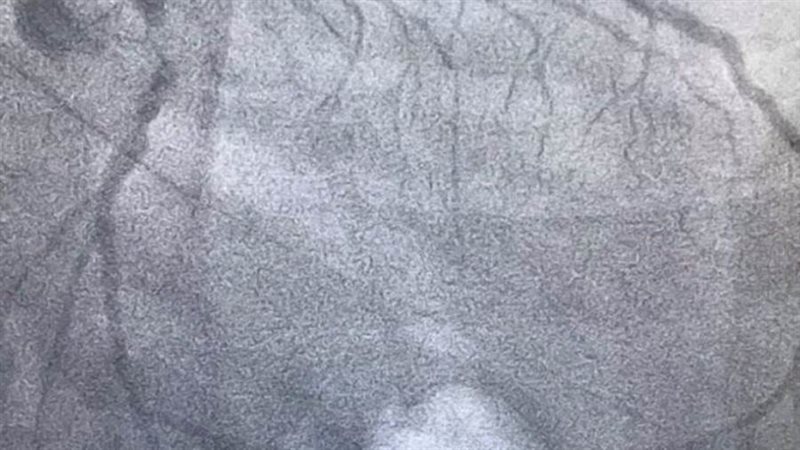

واستقبل المستشفى مريض يبلغ من العمر 65 عاما، ويعاني من وجود ضيق شديد وحرج بالشريان الأمامي النازل، وانسداد مزمن كامل بالشريان المحوري، ما ترتب عليه نقص كفاءة عضلة القلب وإجهاد شديد مع المجهود البسيط بعد تعرضه لذبحات متكررة، وفشلت جميع محاولات المريض لتركيب دعامات.

وتقرر تركيب ثلاث دعامات دوائية بالشريان الأمامي النازل والشريان المحوري، في محاولة لتجنب عمل جراحة قلب مفتوح، ونجحت عملية تركيب الدعامات وخرج المريض بصحة جيدة.